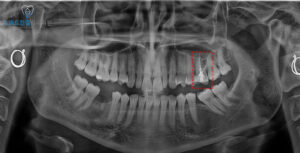

치아의 상태를 더 정밀하게 확인하기 위해

파노라마와 CT 촬영을 진행해본 결과,

치아 뿌리 끝에 염증이 있는

부분이 발견되었어요.

특히, 이 병소는 치아의 뿌리와

가까운 부위에 위치해 있으며,

상악동(코 위의 빈 공간)과

연결된 모습이 보였는데요.

기존 치료 시 메탈 포스트를 활용하여

신경치료가 이루어졌으나,

염증이 발생한 근관이 아닌

다른 근관에 포스트가

삽입된 상태였는데요.

이를 통해 염증이 있는 부위에

접근할 수 있다고 판단하여,

우선적으로 재신경치료를 진행하기로 했어요.